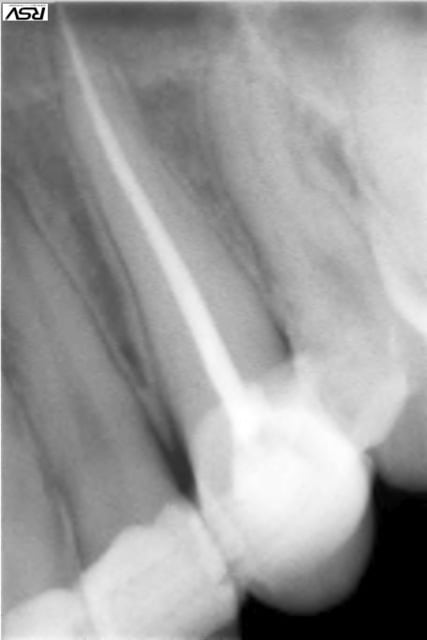

Patient de 20 ans venu en Urg cette après midi:

dent perdue temps moins de 2h

Suite à appel gardée en bouche

Bio réalisée dans une compresse stérile

Réimplantation après rinçage alvéole sérum Phy

Contention au Ribbond + compo , pas facile quand çà saigne

AB pendant 6 jours + Chx.

J'ai juste un doute en ce qui concerne l'hypochlorite , je ne m'en suis pas servi pour rincer le canal de peur de finir d'achever les quelques fibroblastes présents sur le cément du coup j'ai rincer le canal au sérum phy.

désolé pour l'ordre des photos